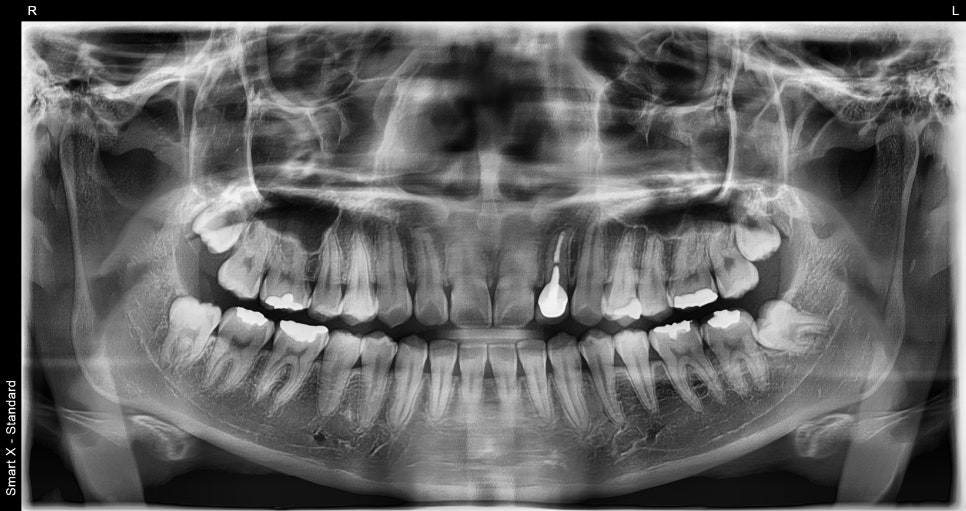

📸 발치 전 X-ray 사진

발치 전, 완전 매복 사랑니가 뼛속 깊이 파묻혀 있는 모습입니다.

📸 발치 후 X-ray 사진

네 개의 사랑니를 한 번에 발치한 후 촬영한 파노라마 사진입니다. 발치 부위가 깔끔하게 정리된 것을 확인할 수 있습니다.

수술 전에는 사랑니가 뼛속 깊이 매복되어 있었고, 신경과 아주 가까워 조심스럽게 수술 접근이 필요했어요.

수술 후에는 깨끗하게 회복되고 있고, 신경 손상 없이 마무리되었습니다. 😊